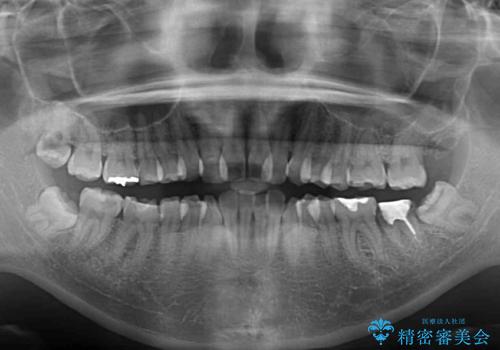

目立たない装置を希望されたので、上顎が裏側装置のハーフリンガルを選択し、上下左右の小臼歯(計4歯)を抜歯して矯正治療を行うこととしました。

また、左下の奥歯は抜歯が必要な歯であったため、矯正治療中の良いタイミングで抜歯とインプラント埋入を行い、矯正治療後にオールセラミッククラウンで補綴治療を行うこととしました。

デコボコの解消までは非常にスムーズでしたが、咬合力が強いためか、スペースを閉じるまでに長い期間を要しました。

矯正治療途中にインプラント埋入と仮歯の装着を行ったことで、しっかりとした奥歯の咬み合わせで終了させることができました。